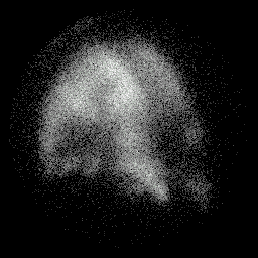

Example of COAD

L Post Oblique Perfusion L Post Oblique Ventilation

match_perf2.gif (20587 bytes) match_vent2.gif (15469 bytes)